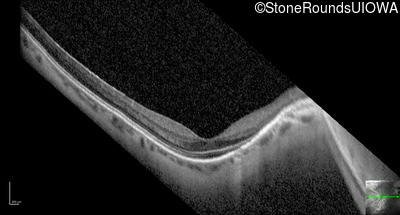

Optical Coherence Tomography - Left - 20/25 +2

Exemplar / OCT Stack

OCT Stack